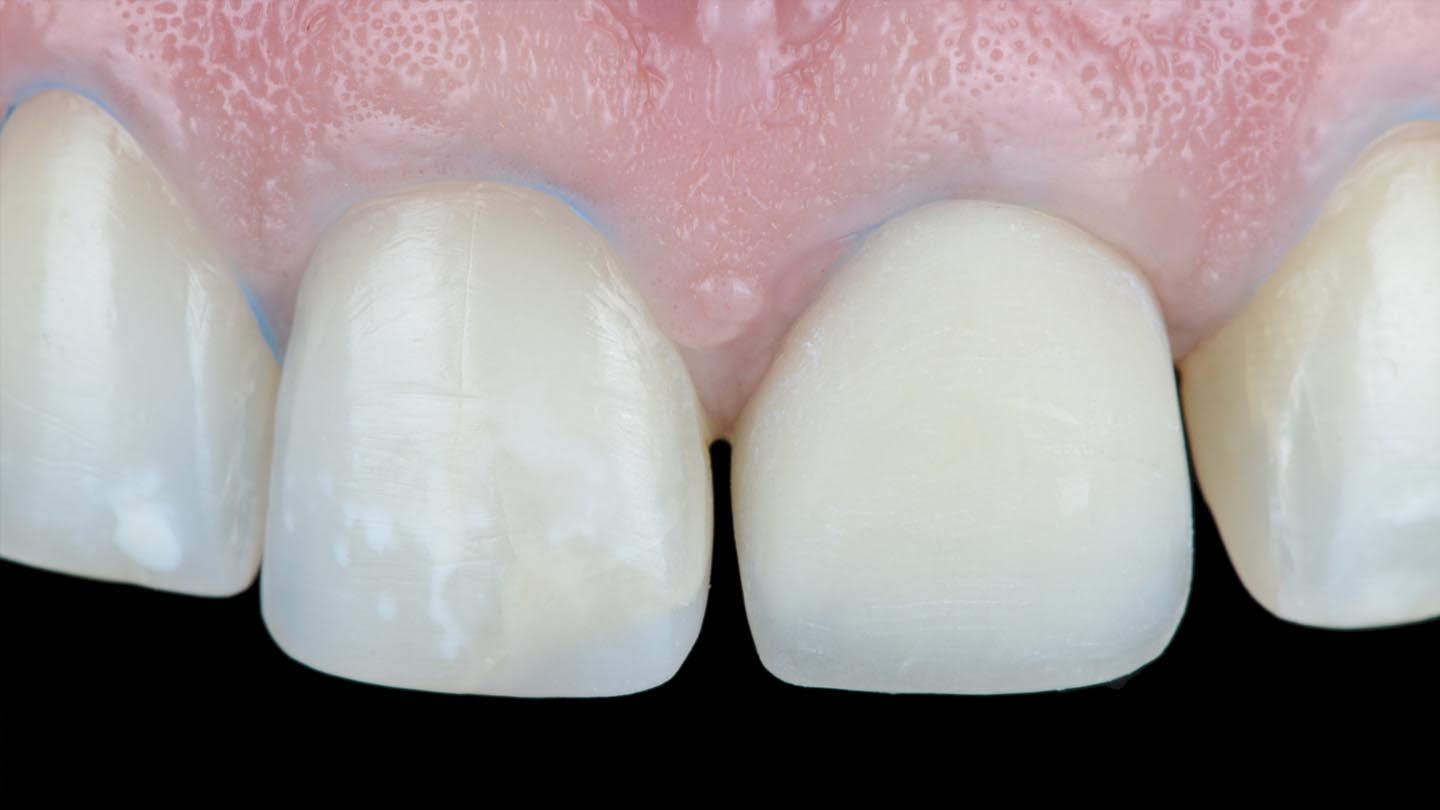

The opaque-core crown was tried-in on tooth No. 9 and approved in terms of marginal fit, preparation adaptation, and shade matching with the adjacent incisors. After this assessment, the crown was prepared, similar to the remaining teeth, to receive a ceramic veneer. A new digital intraoral final impression (TRIOS 4) was made for all four maxillary incisors, and the standard tessellation language (STL) files were sent to the laboratory for the manufacture of lithium-disilicate porcelain veneers (IPS e.max) using subtractive milling technology (PrograMill® PM5, Ivoclar). All data transfer from 3D planning to the laboratory CAD/CAM process is faster, easier, and more predictable than conventional methods, resulting in less manufacturing time and chairtime and enhanced final esthetic results (Figure 7 and Figure 8).16-18

After the luting procedure was completed, a water-based gel was applied to the margins of the restorations to eliminate the oxygen-inhibited layer, and then light-curing was performed for 60 seconds on each veneer. Centric and eccentric contacts were verified using articulating paper. The final results demonstrated the integration of the restorations with natural texture and morphology and an accurate shade matching (Figure 18 and Figure 19). Based on the authors’ experience, these procedures are best performed under magnification.